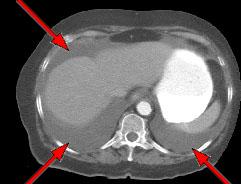

HELICAL CT FINDINGS: The CT was performed on AIC’s multi-slice helical CT (MSCT) scanner. Images with 5 mm collimation were obtained before, immediately following and 5-10 minutes after power injection of IV contrast. Fig. 1 demonstrates large bilateral pleural effusions (red arrows) with secondary compressive atelectasis of the lower lobes (yellow arrow). Fig. 2 shows large amount of ascites (arrows). Fig. 3 shows a large heterogeneous complex pelvic mass (blue arrow) and a large amount of peritoneal masses consistent with omental metastasis known as “omental caking” (green arrows).